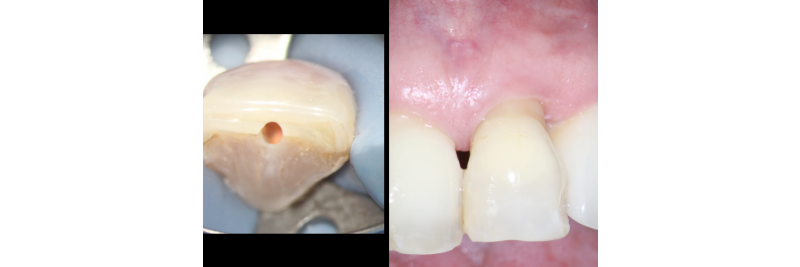

It must be stated that ample access preparation (Figs. 2A, 2B) is not required to internally bleach non-vital teeth, as a larger access preparation further compromises the tooth structurally. Figures 3A and 3B illustrate successful outcomes with a much more conservative approach (treatment by Dr. Steve Baerg, Gig Harbor, Washington).